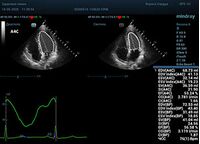

С появлением В режима реализовалась возможность визуализации всех сегментов миокарда из парастернальных и апикальных сечений. Метод Teicholtz в широкой практике сменился методом дисков. Метод дисков, или метод Simpson, позволяет разбить левый желудочек на 20 дисков, с расчетом объема каждого из них. Используя 2 перпендикулярных сечения, апикальные двух и четырех камерное, мы приближаемся к значению реального объема левого желудочка. Исследователь обводит интерфейс эндокард – кровь в фазу диастолы и фазу систолы. Линия простирается от кольца митрального клапана и до кольца митрального клапана, четко разграничивая объем желудочка от предсердия. Для достоверного изменения необходимо использовать ЭКГ канал.

Что могут предложить современные приборы? Приборы нашего времени являются мощными вычислительными машинами, способными обрабатывать полученную информацию даже без помощи человека. Система автоматического вычисления фракции выброса – AUTO EF на приборах серии Resona компании Mindray сделает все за вас. За пару секунд прибор сам отыщет нужную фазу сердечного цикла и произведёт измерение и расчеты, а также покажет график изменения объема в сердечном цикле. От Вас требуется только получить качественное 4С и 2С сечение. Впрочем, прибор всегда оставляет возможность коррекции, если доктор имеет свое мнение на расположение точек планиметрии или момента измерения по ЭКГ каналу.